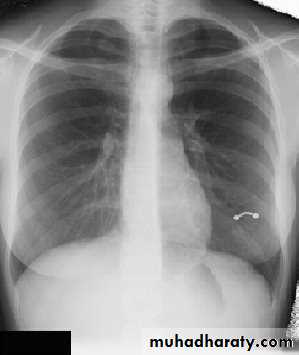

Techniques - Projection

P-A (relation of x-ray beam to patient)Supine view (AP)

Lateral view .

lateral decubitus .(in which the pt put on the suspected side & X-ray is taken (such as in pleural effusion).

LORDOTIC VEIW

Thoracic inlet view : to see hilar shadows, cardiophrenic angle shadow & right middle lobe collapse.

Routine Examination includes

P-A view , Other supplementary views are done according to the case. So all Patients admitted to hospital should have P-A X-ray In standing erect view in complete inspiration